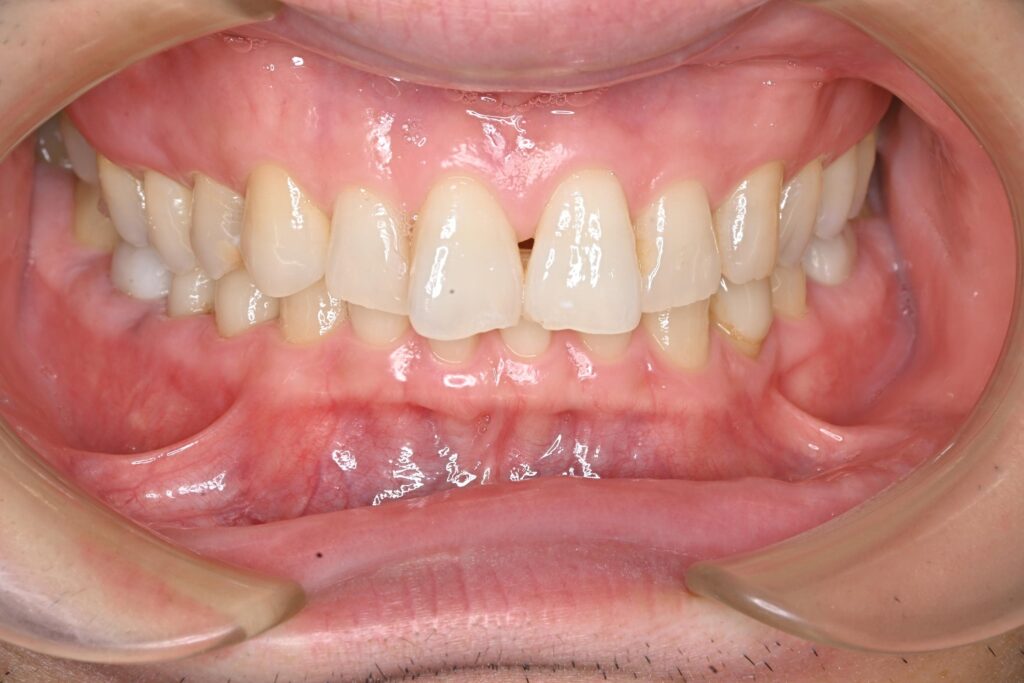

治療結果

全ての金属を非金属素材に置き換え、感染源も除去した結果、治療後は症状が落ち着いている状態が確認されました。 患者様はアレルギーやそれに伴う症状の悩みが大幅に軽減されたようで、非常に喜んでいただけました。

本症例では、金属アレルギーの懸念に加え、古い金属修復物の下に潜んでいた虫歯や感染源を全て取り除き、生体親和性が高く審美性にも優れた非金属素材に置き換えることができました。

After